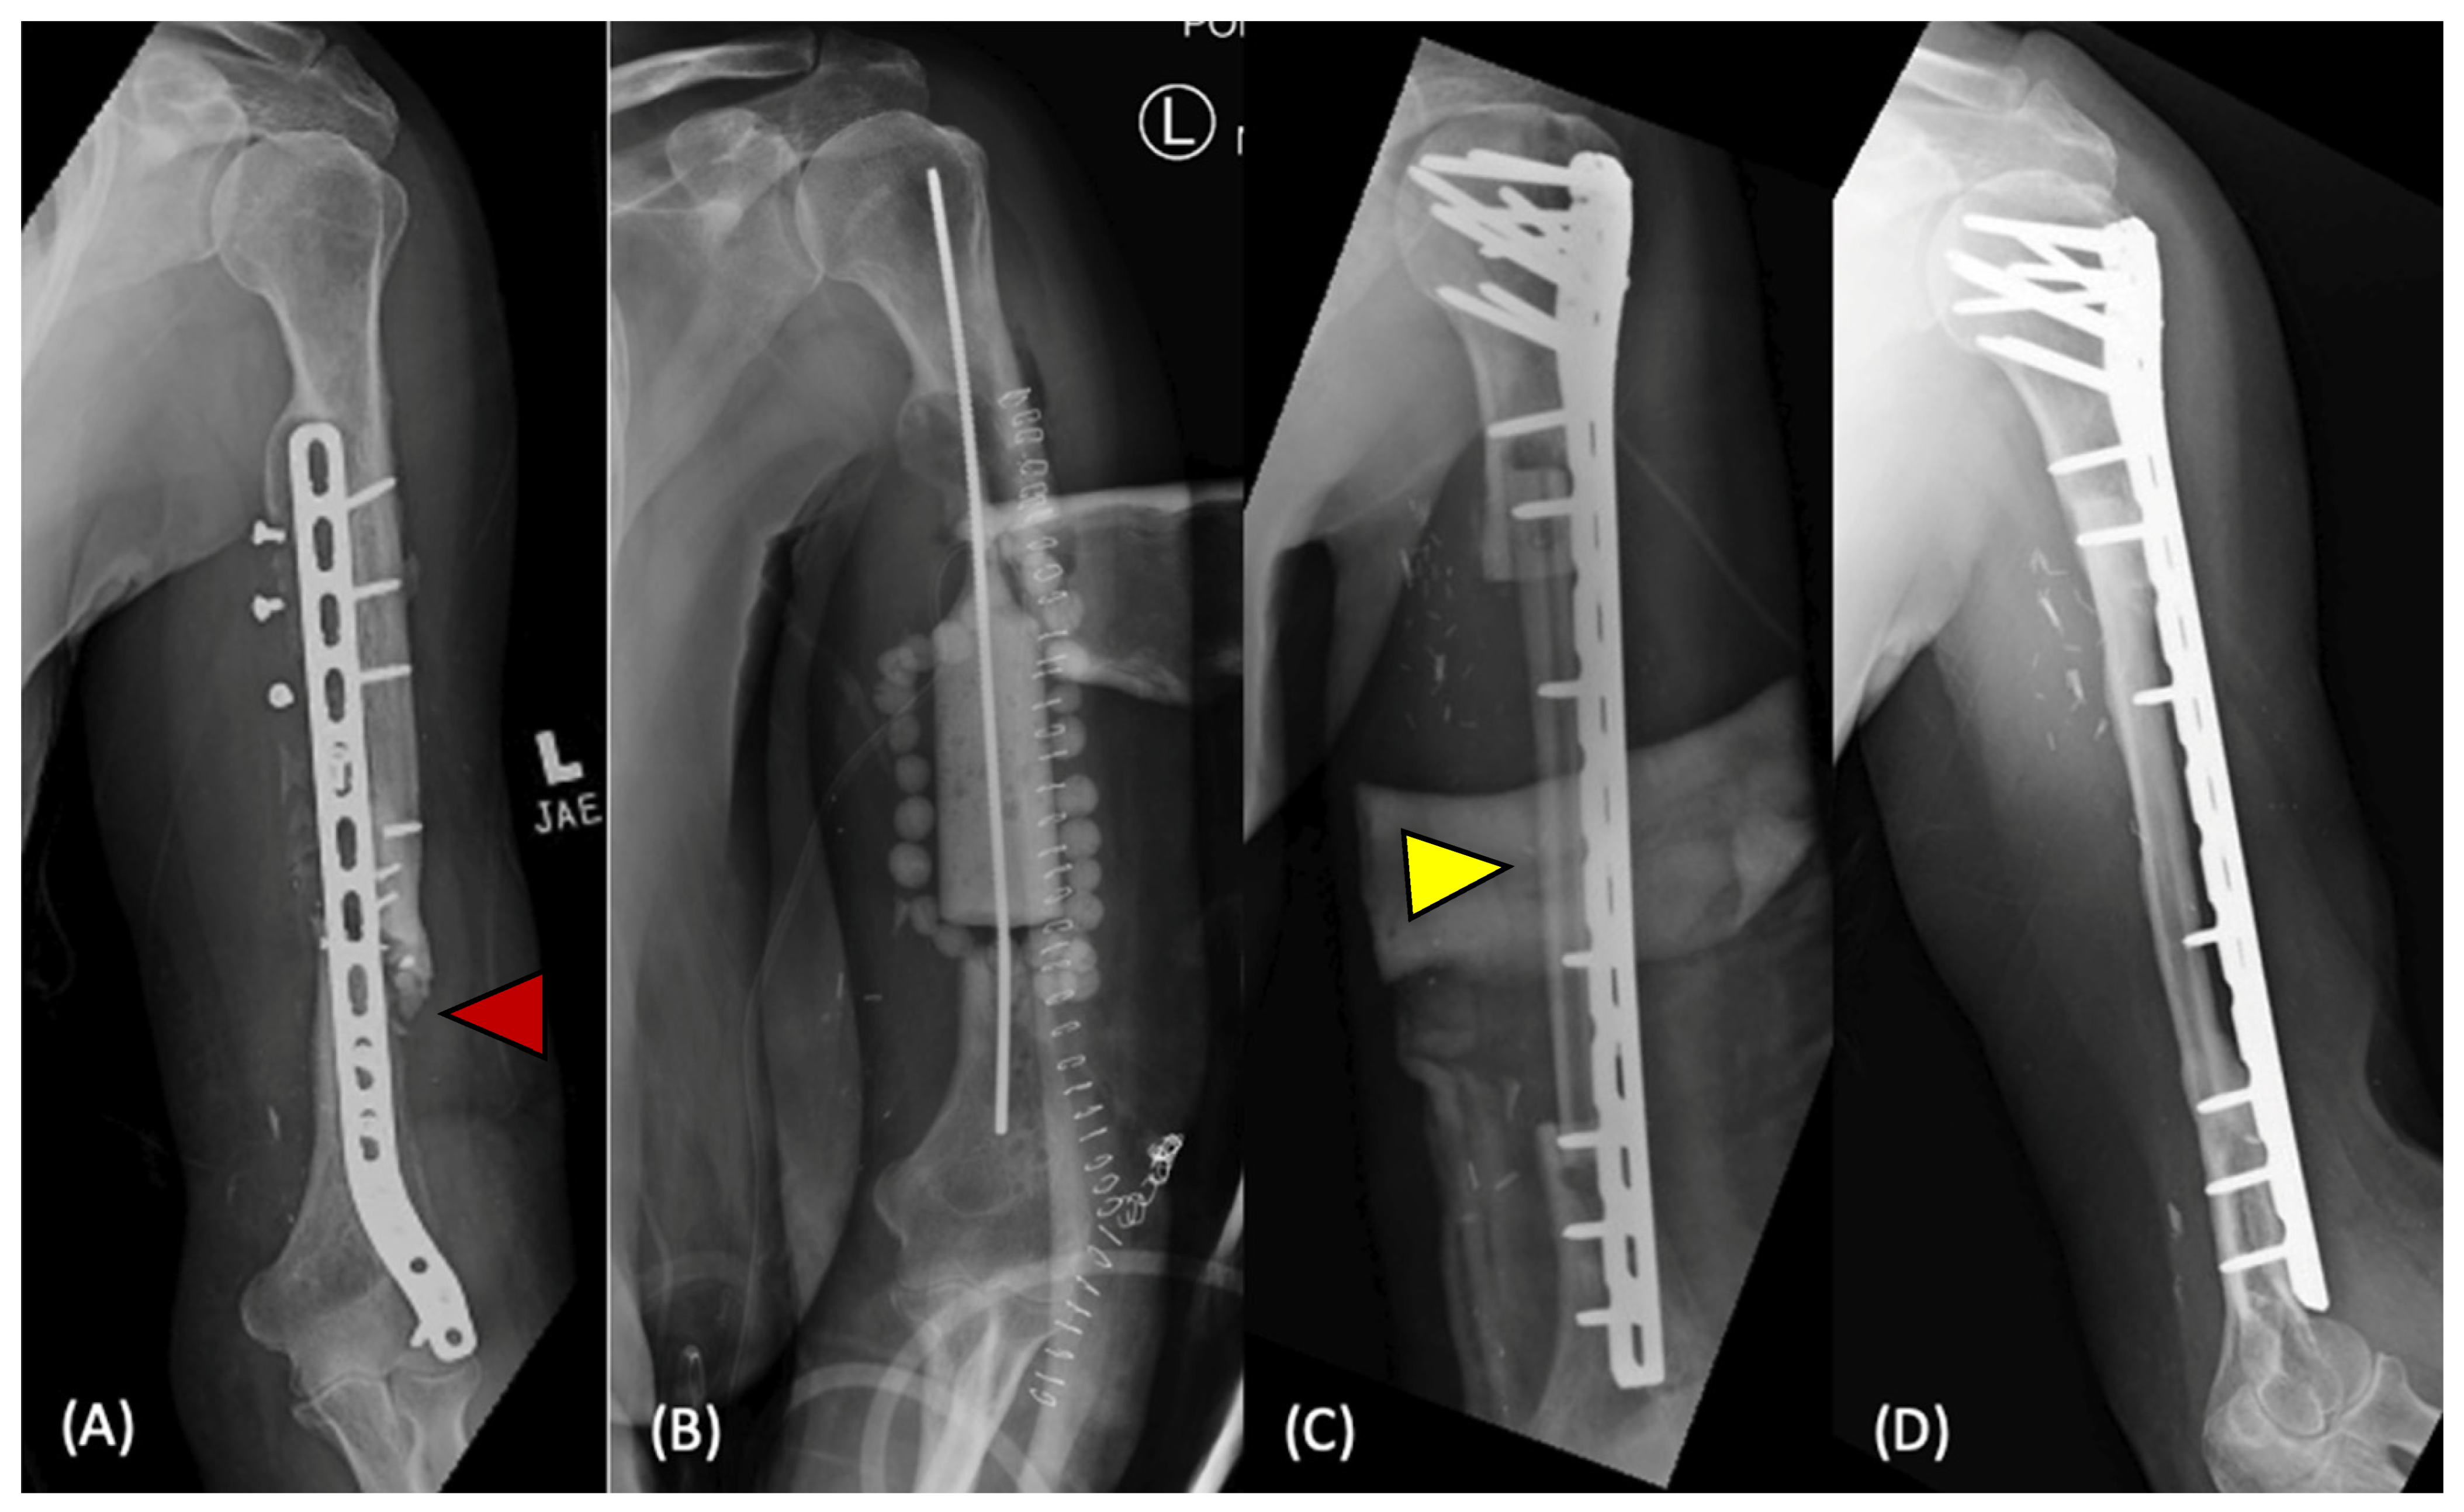

1. Introduction

2.4. Surgical Techniques for Large Defects

2.4.3. Distraction Osteogenesis